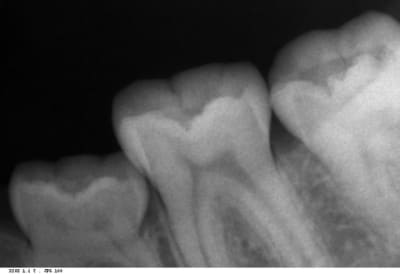

Voici les radios...

vous pouvez remarquer qu'il y a aussi un diasystème entre 34 et 75 ...

75 ghrdn4 - Eugenol

75 2 cyjmtv - Eugenol

Mais au vu de tes radios, on voit bien que la face distale est clairement en dessous du point de contact de tes 6.